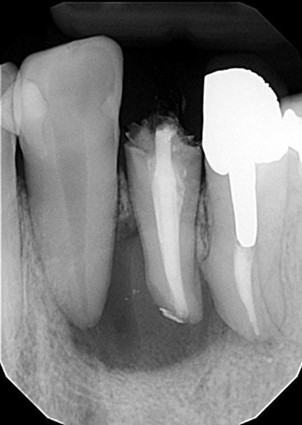

| 主訴 | 歯がしみる・見た目を改善したい |

| 状態 | 完全に神経が見えている状態だったので、根管治療を行ったのちセラミックで審美回復した症例。 |

| 料金 | 根管治療9万円+税、ファイバーコア2万円+税、仮歯1.5万円、E=MAXクラウン11.5万円+税(1本)×2本分=48万円 |

※根管治療と審美は別っていう医院が多いけど、包括的に治療できることが強み